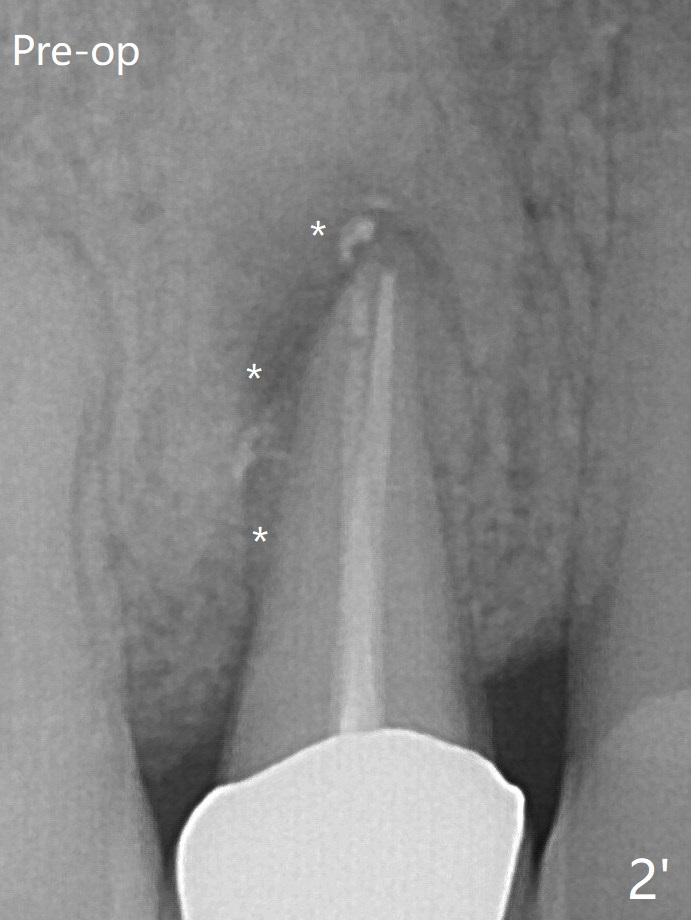

Before placement of a 4.5x17 mm tissue-level implant (Fig.2, (*: bone graft, as compared to preop bone defect (*))) and after osteotomy for bone-level one, PRF and mixture of autogenous bone and allograft are pushed from the socket through the buccal defect for repair (Fig.3 arrowheads).